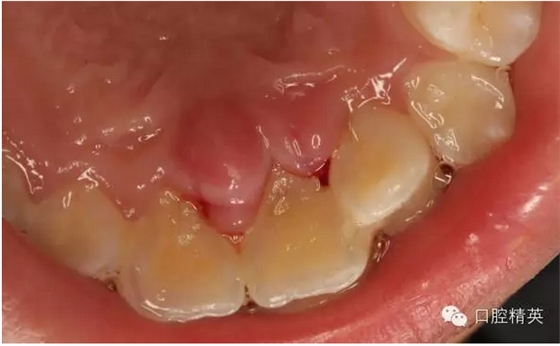

圖2.口內(nèi)整體影像

圖2.拆線前腭側(cè)觀

圖4.腭側(cè)觀21齦乳頭水腫明顯